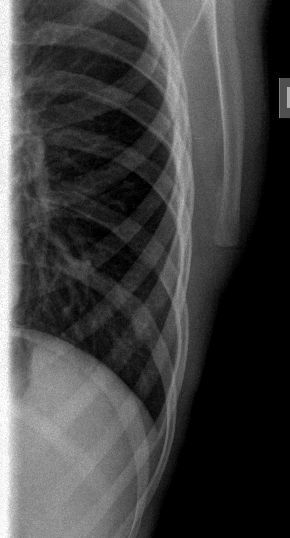

После УЗИ - сделал рентген, изменения в ребре есть, но в глаза не бросаются

Diagnosis of Ewing's Sarcoma is suspected

The irregularity of the rib shown sonographically suggests an osseous process like Ewing sarcoma. However, I have seen three patients with similar findings with destruction of the sternum and adjacent ribs mimicking a tumour of the bone but caused by an infiltration of a Hodgkin’s lymphoma. A lymphoma would also be more consistent with the lesions found in the spleen. Regarding the morphology and shape of the mass in the axilla, I think this is a lymphnode.